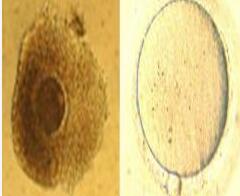

成熟卵体外成熟技术(In Vitro Maturation,IVM)是试管婴儿领域的一项前沿技术,专门针对一些卵子成熟障碍的不孕患者,特别是那些顽固的多囊卵巢综合症、卵泡发育迟缓、卵巢过度刺激征的患者。

将未成熟的卵母细胞取出,在体外进行培养、受精,然后将胚胎移植到母亲子宫腔广州代妈服务内生长。这种技术还可能避免药物和治疗的副作用,减少费用,降低促排卵的风险。